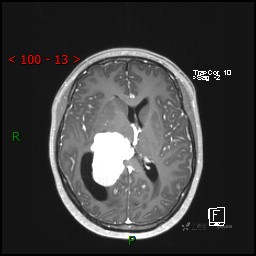

视物模糊发现颅内占位,“豆蔻年华”却承受开颅之痛,所幸一切顺利---结果公布~

患者年龄:14岁

简要病史:患者于1月前无明显诱因出现视物模糊,无明显头痛头晕,无恶心呕吐,无昏迷,无肢体偏瘫等症状,就诊于当地医院头部CT考虑:右侧丘脑、脑室占位。予以对症处置后家属为求进一步诊治来我科,以“颅内占位”收入院。 起病以来,精神、饮食、睡眠欠佳,大小便正常,体力下降,体重无明显变化。

临床诊断:脑室占位

MRI平扫